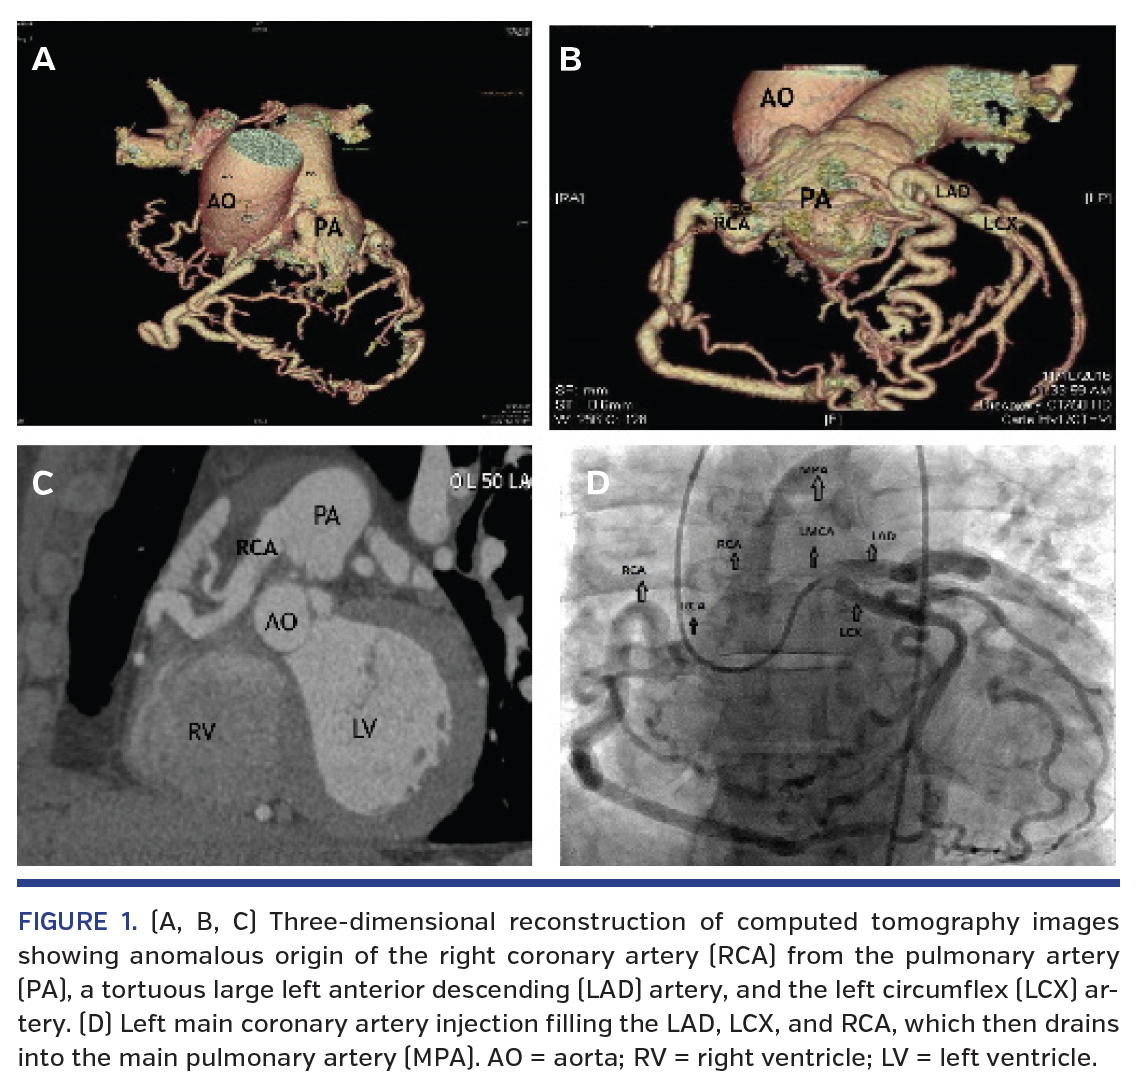

A 55-year-old man presented with altered mental status and hypoxia due to opiate drug abuse. Due to elevated cardiac troponin, he underwent coronary angiogram. Findings included a large tortuous left anterior descending (LAD) artery and left circumflex (LCX) artery that collateralized to a large right coronary artery (RCA), which drained into the pulmonary artery (PA). Computed tomography angiographic and fluoroscopic images confirmed anomalous RCA from PA (ARCAPA) (Figure 1 and Video 1). Epicardial coronaries were without any significant obstructive disease. Oximetry was performed to determine the significance of left to right shunt; however, there was no hemodynamically significant step-up in oxygen saturation from right ventricle to PA, suggesting that the shunt was not significant. The cardiac enzyme elevation was attributed to hypoxia-related stress on myocardium in the presence of ARCAPA. Cardiothoracic surgical consultation was done at our center and the patient was referred to another center to an adult congenital heart disease surgeon. ARCAPA is exceedingly rare, with reported incidence of 0.002% in the literature. Coronary steal phenomenon can occur in ARCAPA due to differences in diastolic pressure between systemic and pulmonary arterial beds, with risk of myocardial ischemia during increased myocardial oxygen demand. Surgical correction with implantation of anomalous RCA into the aorta is recommended.